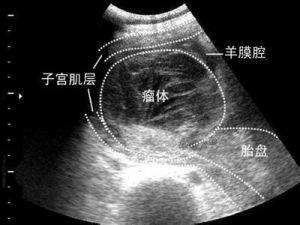

7.胎盤血管瘤(亦稱絨毛血管瘤)和胚胎囊腫:此類少見,一般對胎兒無影響。